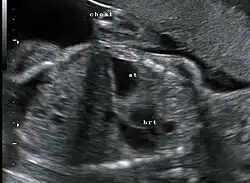

This condition can often be diagnosed before birth and fetal intervention can sometimes help, depending on the severity of the condition.[8] Infants born with diaphragmatic hernia experience respiratory failure due to both pulmonary hypertension and pulmonary hypoplasia. The first condition is a restriction of blood flow through the lungs thought to be caused by defects in the lung. Pulmonary hypoplasia or decreased lung volume is directly related to the abdominal organs presence in the chest cavity which causes the lungs to be severely undersized, especially on the side of the hernia.

Survival rates for infants with this condition vary, but have generally been increasing through advances in neonatal medicine. Work has been done to correlate survival rates to ultrasound measurements of the lung volume as compared to the baby's head circumference. This figure known as the lung-to-head ratio (LHR). Still, LHR remains an inconsistent measure of survival. Outcomes of CDH are largely dependent on the severity of the defect and the appropriate timing of treatment.